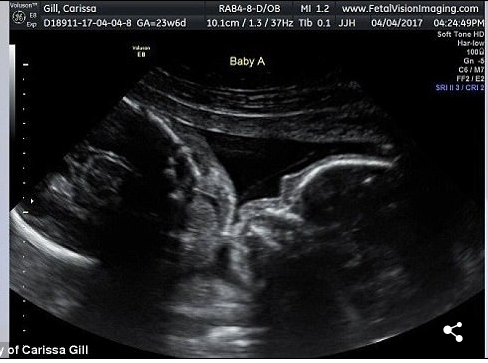

Veja mais fotos do Ultrassom de Carissa: